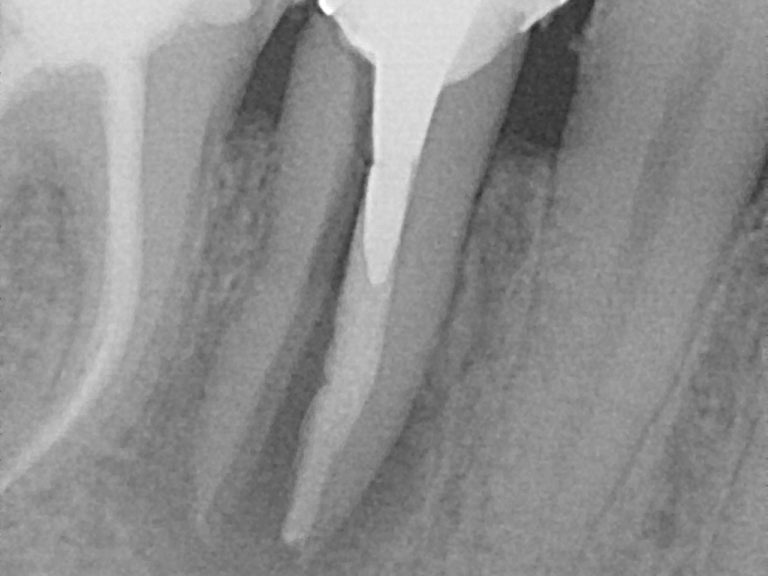

Chirurgie endodontique (apicale)

Lorsque l'infection persiste après un traitement de canal (dévitalisation), on retire chirurgicalement l'extrémité de la racine et les tissus infectés.